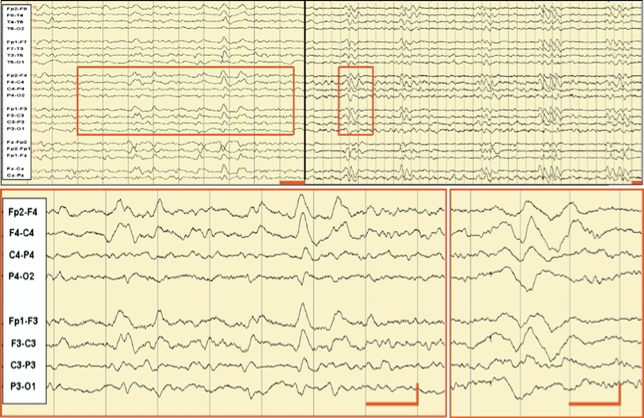

认识克雅氏病的脑电图表现

图片尺寸644x418